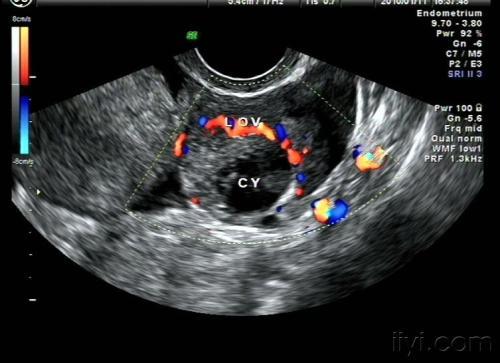

我们又把小唐扶到了床上,进行身体检查,姜医生腹部检查发现,小唐有明显压痛、反跳痛。阴道检查,没有发现阴道出血,子宫正常大小,后穹窿触痛,附件可触及境界不清的软包块,有压痛。

为了确诊,姜医生又对小唐进行了阴道后穹窿穿刺,果然发现有内出血的症状,确诊为黄体破裂。